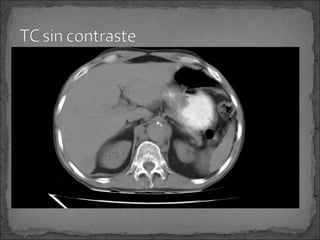

Siempre que se sospeche de D.A. se debe de tener

siempre una TC sin medio de contraste para detectar un

IMH.

No contrastada: Area en forma de luna creciente a nivel

de la pared aórtica. El hematoma puede o no comprimir

la luz aórtica o desplazar las calcificaciones de la íntima.